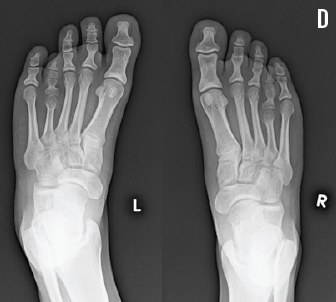

A diagnosis of brachydactyly was considered, and radiographs were obtained. The hand radiographs showed bilateral shortened fifth metacarpal bones and bilateral shortened fifth fingers middle phalanges (C). The foot films showed bilateral shortened fourth metatarsal bones (D). The final diagnosis was bilateral brachymetacarpia and brachymetatarsia.

Physical examination results were within normal limits except for a bilateral shortening deformity of the fourth toes, which slightly overlapped the adjacent fifth toes (A). According to her mother, the girl was noted to have had changes in her toes’ appearance since early childhood. Nevertheless, the changes were not interfering with her usual (and often strenuous) daily activities. A careful examination of her hands also revealed bilateral shortening of the fifth fingers, with questionable shortening of the thumbs (B). The girl’s maternal aunt had had a similar finding in her toes, but not her fingers.